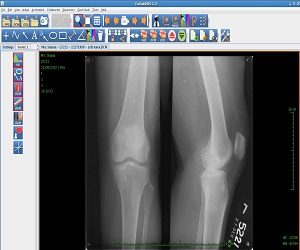

CollabDDS provides a real time collaborative environment to visualize medical (Skeletal) and dental images (digitized X-Ray images or DICOM data) for diagnosis and treatment planning. CollabDDS has various image processing tools to visualize the data and also annotate. An inbuilt repository of annotated images can be used for education. Further it enables real time collaboration for diagnosis between physician at PHC level and experts at medical colleges and hospitals. CollabDDS is unique as it allows the viewing and processing of digitized X-Rays in various standard image formats like JPEG and DICOM and also allows this data to be saved for later review/ study.

The patient submits his/her X-Ray to the Primary Health Center or Secondary Health Center. This is transmitted to the connected higher level centers after scanning it. The digitizer at the time of scanning permits the technician to enter certain details and have the X-Ray in DICOM format if required. DICOM files along with the relevant diagnosis are stored in the Repository at the data center to be accessible for any future reference and teaching purposes.

With the proof of concept having gone through successfully, a Pilot Project for Implementation of CollabDDS at Medical and Dental Colleges and Hospitals has been undertaken. This is an extension of the POC to the Operational Research Phase as a prelim to rollout. This pilot implementation is used to evaluate the efficiency and effectiveness of remote diagnosis. Further this phase also incorporates a module which carries out Cephalometric analysis for orthodontic surgeons to enable diagnosis and treatment planning of their patients. This phase would also include the Enhancement of CollabDDS and Advanced Applications on 3D imaging. It would involve the reconstruction of 3-D models from CT / Surface images, development of methodologies for orthopedic implant development using 3D models.